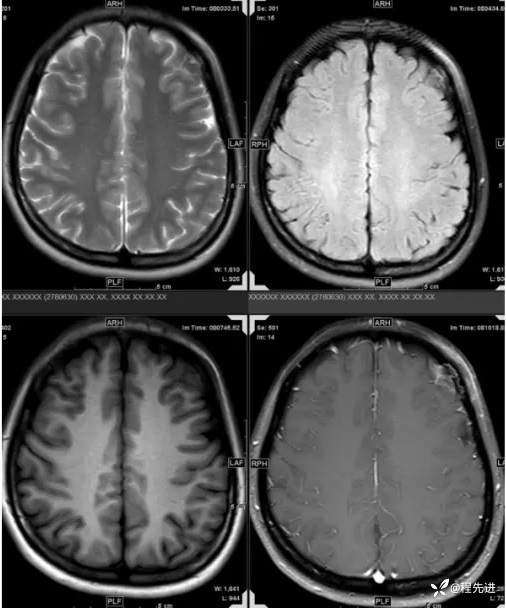

【患者信息】:女,31岁

【主诉】:发现头部肿物1月余

【现病史及既往史】:患者自诉于1月前无明显诱因出现左额颞部肿块,大小约3*3cm,伴疼痛红肿发热,遂至我院外科门诊就诊考虑“局部感染”,予以对症治疗后,肿块疼痛红肿好转,但肿块无明显缩小。

【检查】:常规检验项目均(-)